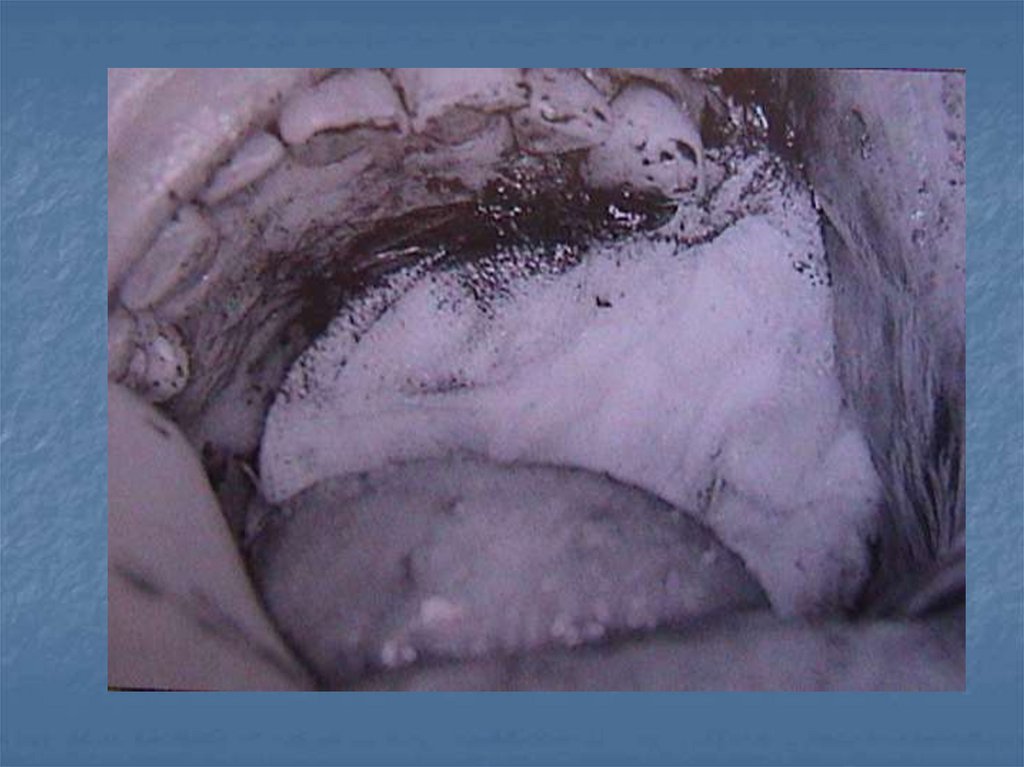

İmmediat protezlerin hazırlanması

Obturatörleri Etkileyen Kuvvetler-2